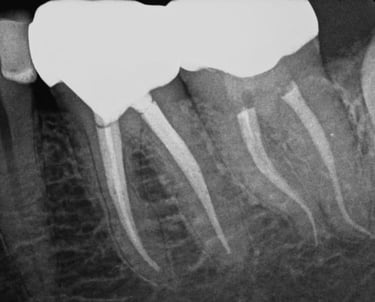

Cuando una caries profunda o un traumatismo alcanzan el nervio dental, es necesario realizar una endodoncia para conservar la pieza.

En IdenClinic eliminamos el tejido infectado del interior del diente y sellamos los conductos radiculares con máxima precisión, utilizando instrumentación rotatoria y control digital de longitud.

Este procedimiento detiene la infección, alivia el dolor y evita la extracción. Posteriormente, reforzamos el diente con una reconstrucción o corona protectora, devolviéndole su funcionalidad y aspecto natural para una salud bucal a largo plazo.

ENDODONCIA